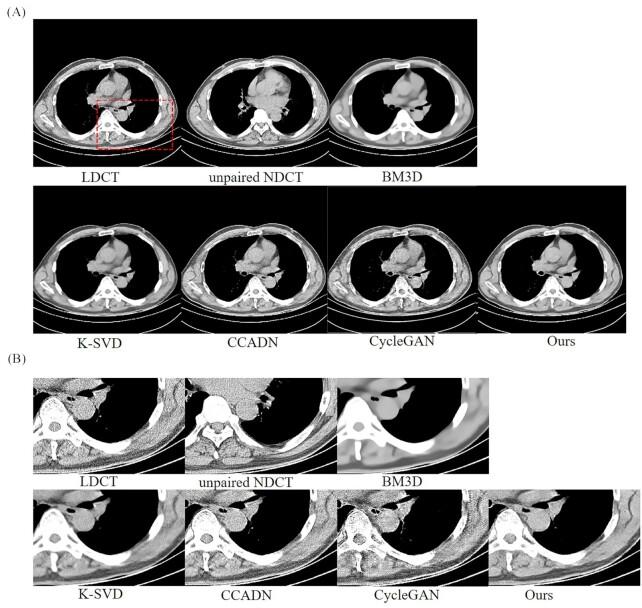

Low-dose computed tomography (LDCT) denoising is an indispensable procedure in the medical imaging field, which not only improves image quality, but can mitigate the potential hazard to patients caused by routine doses. Despite the improvement in performance of the cycle-consistent generative adversarial network (CycleGAN) due to the well-paired CT images shortage, there is still a need to further reduce image noise while retaining detailed features. Inspired by the residual encoder-decoder convolutional neural network (RED-CNN) and U-Net, we propose a novel unsupervised model using CycleGAN for LDCT imaging, which injects a two-sided network into selective kernel networks (SK-NET) to adaptively select features, and uses the patchGAN discriminator to generate CT images with more detail maintenance, aided by added perceptual loss. Based on patch-based training, the experimental results demonstrated that the proposed SKFCycleGAN outperforms competing methods in both a clinical dataset and the Mayo dataset. The main advantages of our method lie in noise suppression and edge preservation.

低剂量计算机断层扫描(LDCT)去噪是医学成像领域不可或缺的一项操作,它不仅能提高图像质量,还能减轻常规剂量对患者造成的潜在危害。尽管由于配对良好的CT图像短缺,循环一致生成对抗网络(CycleGAN)的性能有所提升,但仍需要在保留细节特征的同时进一步降低图像噪声。受残差编码器-解码器卷积神经网络(RED-CNN)和U-Net的启发,我们提出了一种用于LDCT成像的新型无监督模型,该模型使用CycleGAN,将双边网络注入选择性内核网络(SK-NET)以自适应选择特征,并使用PatchGAN鉴别器生成具有更多细节保留的CT图像,同时添加感知损失作为辅助。基于基于补丁的训练,实验结果表明,所提出的SKFCycleGAN在临床数据集和梅奥数据集中均优于竞争方法。我们方法的主要优点在于噪声抑制和边缘保留。